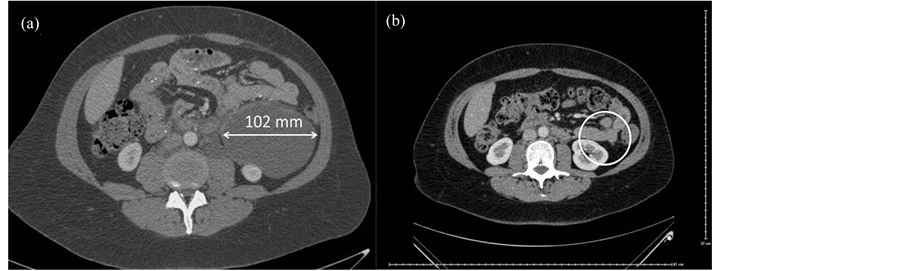

Bilateral LuTX was performed in Vienna in January 2012. Postoperatively she received triple immunosuppressive therapy including tacrolimus, mycophenolate mofetil and prednisolon. After two weeks surveillance bronchoscopy confirmed A2B1-2 rejection, following steroid shot treatment control transbronchial lung biopsy was negative for rejection (A0B0). Lung function has been gradually improving. The six-month chest-abdo- minal CT scan showed an enlargement in the angiomyolipoma located in the upper RP (Figure 1(a)) compared to the preoperative state. In October 2012, 9 months after TX everolimus (plasma level: 2.31 ng/ml) was added to tacrolimus (plasma level: 7.7 ng/ml) therapy, while combination with mycophenolate mofetil and prednisolon maintained. Six month after the introduction of combination therapy with mTOR inhibitor the angiomyolipoma was not detectable on the one year chest-abdominal CT (Figure 1(b)). The patient is since on everolimus, tacrolimus, mycophenolate mofetil and prednisolon therapy with the same plasma level as the combined therapy started, showing excellent graft function (lung functional values October 2014: FVC 3.63 L (110% predicted), FEV1: 2.59 L (91% predicted), FEV1/FVC: 71%), and no signs of abdominal disease on the abdominal CT scan performed 2 years after LuTX.

Figure 1. (a) Abdominal angiomyolipoma in LAM patient 6 months after LuTX; (b) Complete remission of angiomyolipoma in LAM patient after 6 month of treatment with everolimus- tacrolimus combination therapy.

a low risk of progression and ultrasound follow-ups are sufficient every 1 or 2 years. In our case the angiomyolipoma was asymptomatic, however due to its extent (102 mm) surgical removal might be suggested due the possibility of life-threatening haemorrhage [2] . This benign tumor could not be removed surgically as LAM is a multisystem disease and intervention would not have stopped the development of angiomyolipomas at subsequent sites. Although the tumors have oestrogen and progesterone receptors there is no firm evidence of efficacy of hormone treatment in this disease [2] . A comprehensive study examined the effects of the mTOR inhibitor sirolimus on angiomyolipomas. A 12 month treatment with sirolimus led to significant reduction (53.2% ± 26.6%, p < 0.001) within a group of 25 patients in a phase II study [6] . The efficacy of sirolimus is the result of the known pathomechanism of LAM: tuber in and hamartin proteins are responsible for inhibiting mTOR complex which regulates cell growth. Without this inhibiting signal cell proliferation pathway is uncontrolled [7] . Based on these results and experiences with everolimus in lung transplantation we decided to start treatment with a combination of tacrolimus and everolimus. CT performed 6 months after the combination therapy resulted in complete remission of RP angiomyolipoma. In a previous case report the treatment of angiomyolipoma in LAM patient receiving LuTX included combination therapy of everolimus with cyclosporine, mycophenolatemofetil and steroids. This treatment resulted in a reduction of angiomyolipoma by ~30% after 6 months of treatment [7] . The difference between the effects of cyclosporin and tacrolimus might have a significant impact of everolimus on angiomyolipoma cells.